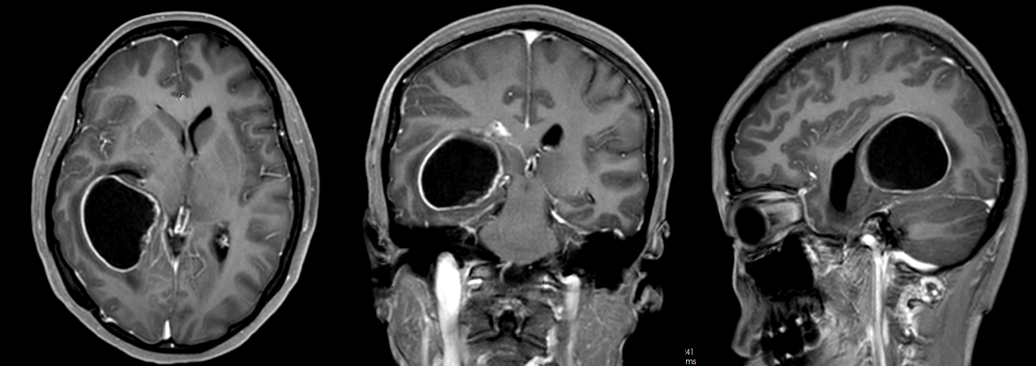

医院接诊时,患者的情况已不容乐观,头痛反复发作,伴有呕吐,逐渐陷入嗜睡状态。急诊完善磁共振,明确患者是颅内占位病变卒中出血,并形成右侧颞角脑积水进行性加重。

甘露醇脱水的效果越来越差,患者颅内这颗“炸弹”正在持续引爆,必须立即干预。医院果断为患者急诊行右侧颞枕叶占位病变切除术手术。

术前影像检查(图源广东三九脑科医院)